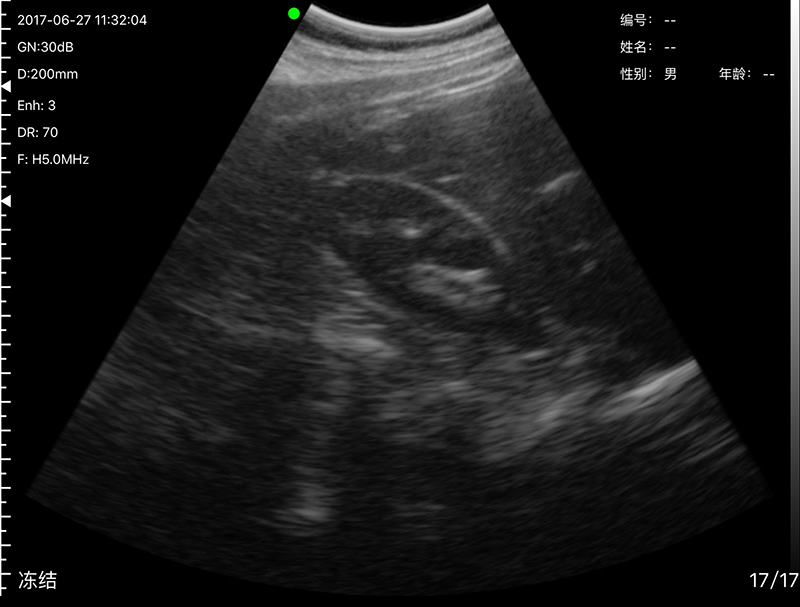

• 穿刺辅助功能:平面内穿刺引导线功能,平面外穿

刺引导与血管自动测量功能,针尖显影增强功能